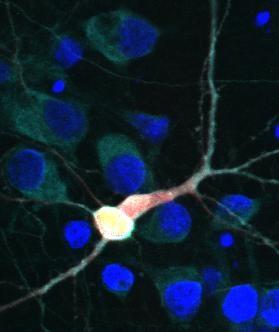

Amyotrophic lateral sclerosis (ALS), also known as Lou Gehrig's disease, is a debilitating neurodegenerative disorder that leads to paralysis and death due to the loss of motor neurons in the brain and spinal cord. A primary feature of ALS is an accumulation of the protein TDP43, too much of which is toxic to cells. In the current study, published in the journal PNAS , the researchers identified another protein, hUPF1, that keeps TDP43 in check, thereby preventing cell death.

Previous investigations had identified hUPF1 as a potential therapeutic target for ALS, but it was unclear how this protein prevented cell death. In the current study, the scientists tested hUPF1's ability to protect against neurodegeneration using a cellular model of ALS. They discovered that genetically increasing levels of hUPF1 extended neuron survival by 50-60%. Digging deeper, the researchers revealed that hUPF1 acts through a cellular surveillance system called nonsense mediated decay, or NMD, to keep TDP43 levels stable and enhance neuronal survival.